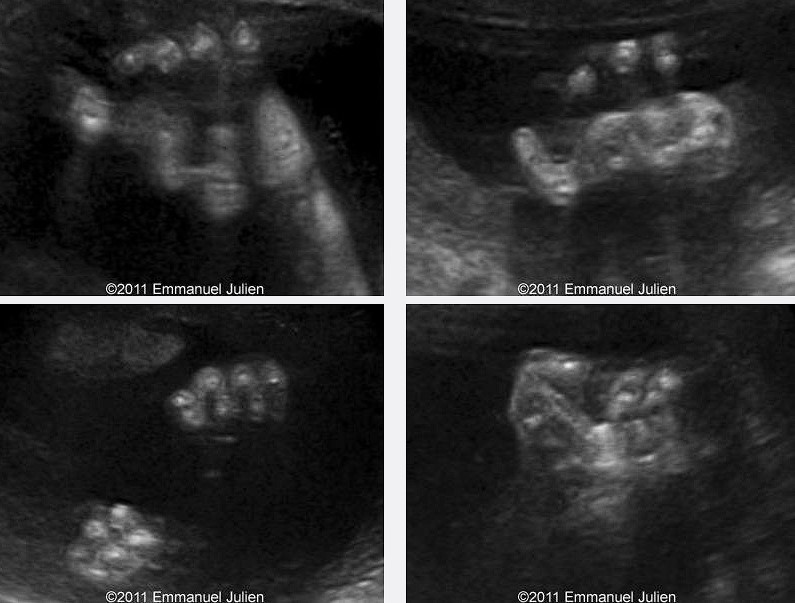

GS tanısı, prenatal (doğum öncesi) dönemde de konabilir. Ultrasonografi, fetüsün eklemlerindeki anormallikleri göstermek için kullanılabilir. Amniyosentez veya koryonik villüs örneklemesi gibi invaziv yöntemler fetüsün DNA’sını almak için kullanılabilir.